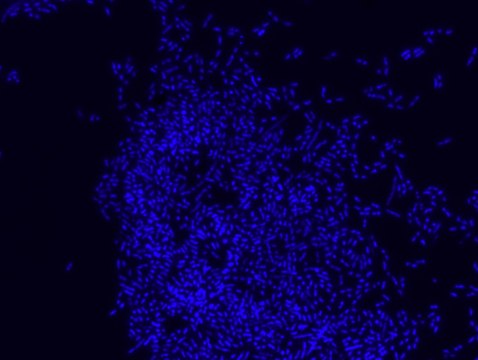

Fluorescent In Situ Hybridization technique (FISH) is based on the hybridization of fluorescent labeled oligonucleotide probe to a specific complementary DNA or RNA sequence in whole and intact cells. Microbial FISH allows the visualization, identification and isolation of bacteria due to recognition of ribosomal RNA also in unculturable samples.

Prokaryotic single cell life forms are divided into two domains, called Bacteria and Archaea, originally categorized as Eubacteria and Archaebacteria. However both terms, Eubacteria and Bacteria are still being used in microbiology. Eubacteria probe recognizes most bacteria as it is complementary to a portion of 16S rRNA found in almost all bacteria.,

FISH technique was successfully used to identify different bacteria with the universal bacterial probe in various samples such as, pure culture (as described in the figure legends), blood cultures,, periapical tooth lesions12, saliva13, biofilms from voice prostheses14, subgingival biofilm15, aortic wall tissue16, buccal epithelial cells, pure culture and cell culture17, intestine tissue embedded in paraffin18, necrotizing fasciitis and pure culture19, colon sections embedded in paraffin20,21, cancer tissues22,23, environmental samples24 and gut of the medicinal leech25. The probe can also be used for combined technique of FISH and Flow cytometric analysis. 9,26,27

Eubacteria FISH probe - ATTO488 is suitable to use as a probe for fluorescence in situ hybridization (FISH) to recognize Eubacteria cells .